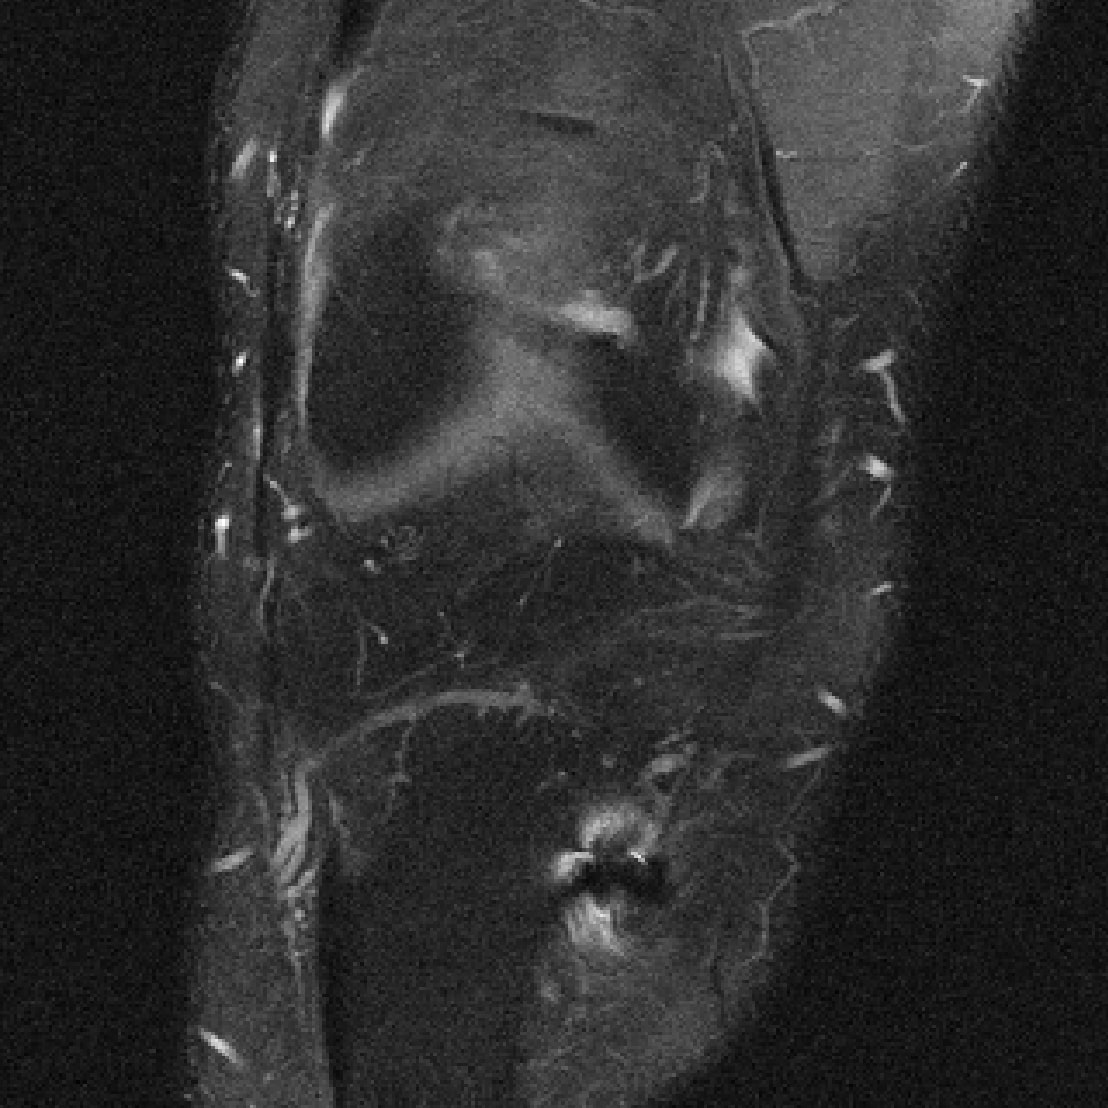

Many of our experiments are based on splits of the fastMRI dataset \citepzbontarFastMRIOpenDataset2019a, the most commonly used dataset for MRI reconstruction research. Figure 2 depicts samples from the fastMRI dataset and shows that MRI data vary in appearance across different anatomies and image contrasts (T1, T2, etc.). The image distribution also varies across vendors and magnetic field strengths of scanners, as the strength of the magnet impacts the signal-to-noise ratio (SNR), with stronger magnets leading to higher SNRs.

The fastMRI dataset stands out for its diversity and size, making it particularly well-suited for exploring how different data distributions can affect the performance of deep learning models for accelerated MRI. In our experiments in Section 3, 4, 5, and 6 we split the fastMRI dataset according to different attributes of the data. In Section 7, we showcase the generalizability of our findings on a diverse collection of 17 different datasets.

We consider two distributions and , and train U-nets \citepronnebergerUNetConvolutionalNetworks2015a, ViTs \citepdosovitskiyImageWorth16x162021b and end-to-end VarNets \citepsriramEndtoEndVariationalNetworks2020b on data from distributions and on data from distribution separately. We also train the same models on data from and , i.e., . We then evaluate on separate test sets from distribution and . We consider the end-to-end VarNet because it is a state-of-the-art model for accelerated MRI, and consider the U-net and ViT as popular baseline models. This diverse selection of architectures (unrolled, convolutional, transformer) aims to demonstrate that our qualitative results are independent of the specific architectural choice. We consider the following choices for and , which are subsets of the fastMRI dataset specified in Figure 2:

Contrasts. We select as PD-weighted knee images from 3 different scanners and are PDFS-weighted knee images from the same 3 scanners.

We are given data from two distributions and , where distribution can be split up into sub-distributions . We consider the following choices for the two distributions, all based on the knee and brain fastMRI datasets illustrated in Figure 2:

Contrast shift: are all FLAIR, T1POST, or T1 brain images and are T2 brain data.